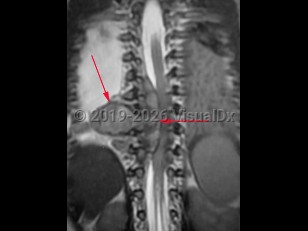

Anemia, Ecchymosis, 50-59 year old Female

Thrombotic thrombocytopenic purpuraThrombotic thrombocytopenic purpura

Chronic kidney diseaseChronic kidney disease

Acute myeloid leukemiaAcute myeloid leukemia

Chronic myeloid leukemiaChronic myeloid leukemia

Acute lymphoid leukemiaAcute lymphoid leukemia

Acute promyelocytic leukemia

Chronic lymphocytic leukemiaChronic lymphocytic leukemia

Aplastic anemiaAplastic anemia

Multiple myelomaMultiple myeloma

Myelodysplastic syndromes